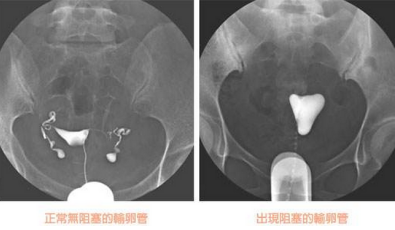

输卵管造影检查,精准了解输卵管病变情况

输卵管造影是用来检查女性输卵管通畅与否的一种检测方法。目前,输卵管造影是临床上应用较为广泛的方法之一。造影是通过导管经阴道、宫颈、子宫腔直接插向子宫角的输卵管开口处,对着输卵管推注造影剂而使输卵管显影,进而了解输卵管是否通畅、阻塞部位及宫腔形态的一种检查方法。